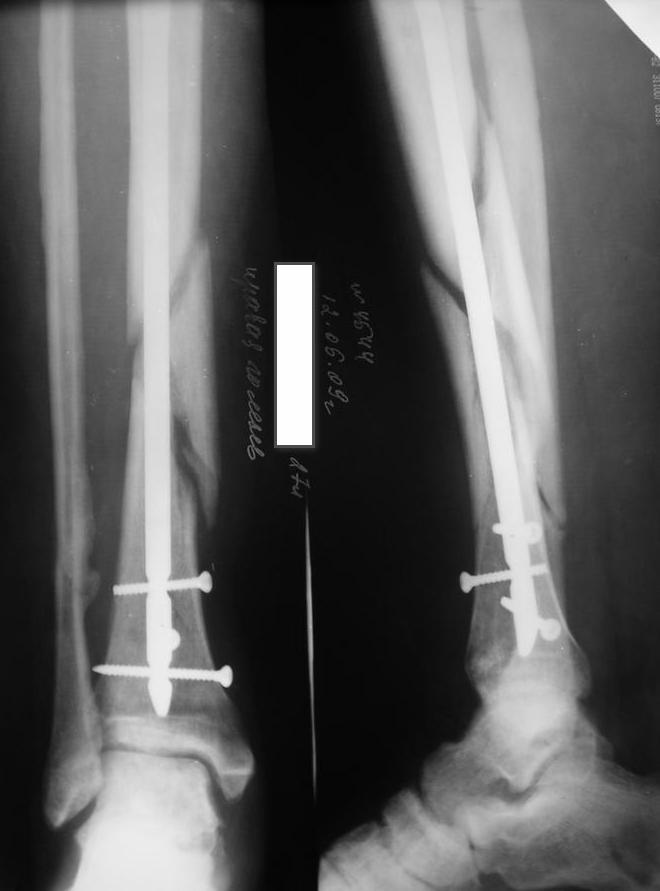

Мне кажется, что необходимо выполнить динамизацию, одновременно выполнив остеотомию малоберцовой кости, т.к. у нее консолидация есть. В дальнейшем ходьба с дополнительной опорой и потепенным увеличением нагрузки около 25% в неделю с выходом до полной на 4-й неделе.

+ osteotomy of fibula++++++++dynamisation

Господа,никаких признаков консолидации нет.Если где-то кажется,то это только за счет укладки(все снимки по-моему с разной укладкой).

Я бы сделал так:произвел бы закрытый остеосинтез по Илизарову,не вынимая штифт,с остеотомией малоберцовой кости и одновременно(одномоментно)-операция туннелизации места перелома по Беку.После этого на операционном столе же удалить шурупы из штифта и производить плановую дистракцию.

По-моему, оптимальное решение уже прозвучало дважды: динамизация+остеоклазия(остеотомия) малоберцовой.